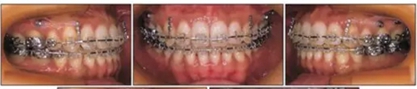

局麻下于植入支抗釘,上頜植入部位在雙側(cè)第二前磨牙和第一磨牙間以及雙側(cè)第一磨牙和第二磨牙間頰側(cè)牙槽骨,下頜植入部位在雙側(cè)第二前磨牙和第一磨牙間間頰側(cè)牙槽骨。植入四周后,用鏈圈連接支抗釘和片斷弓進行磨牙壓低。11個月后,覆合從-3.5mm增大到0.5mm (Figure 6)。在此期間沒有出現(xiàn)顳下頜關(guān)節(jié)癥狀。覆合覆蓋分別為0.5mm和3.5mm。頭測分析顯示有下頜骨旋轉(zhuǎn)(FMA, 46.7°to 44.0°)。移除下頜支抗釘和舌弓。

然后拔除下頜第二前磨牙,開始綜合正畸治療,解除前牙擁擠,并通過遠中移動上牙列獲得I類磨牙關(guān)系(Figure 7)。